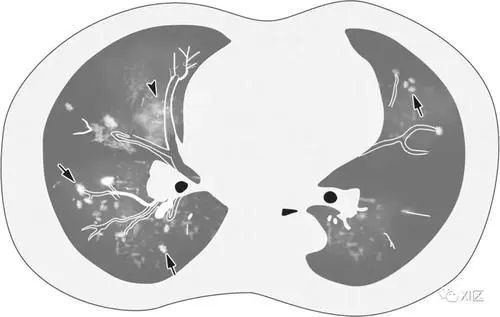

AIDS患者CMV肺炎無(wú)特異性,常合并全身CMV感染,如視網(wǎng)膜炎、結(jié)腸炎、膽管炎和食管炎。胸片和CT常見(jiàn)兩肺毛玻璃樣、粟粒樣或結(jié)節(jié)樣改變。血常規(guī)提示周圍白細(xì)胞的下降。

(1)胸部X線:于病初可能無(wú)異常發(fā)現(xiàn)。隨病情進(jìn)展?jié)u出現(xiàn)兩側(cè)彌漫性間質(zhì)性肺炎或肺泡浸潤(rùn),常開(kāi)始于肺的外周部位,累及肺底。